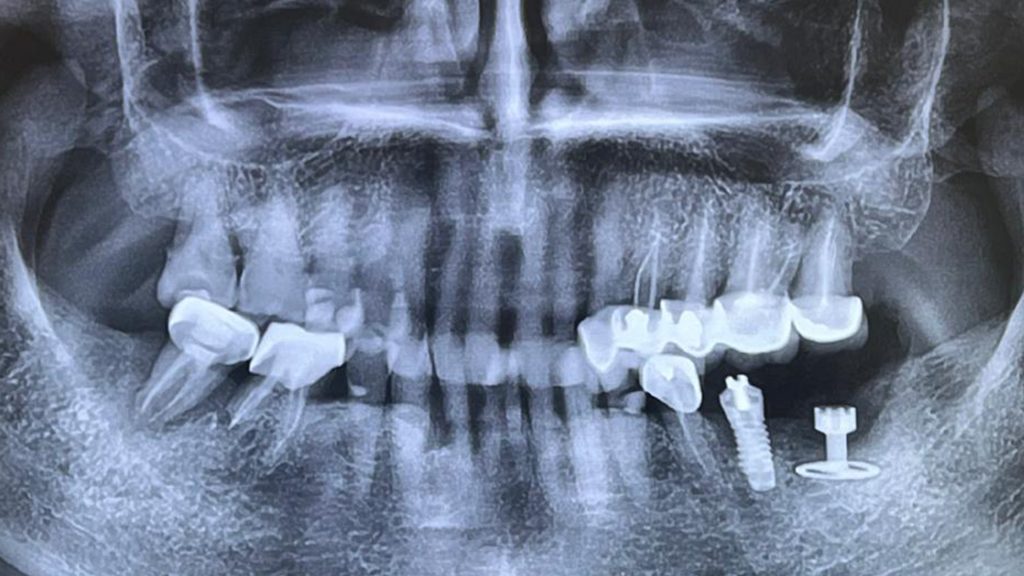

En amont, une activation ostéogénique avait été mise en œuvre, permettant d’initier un processus de régénération osseuse favorable.

Après une anesthésie loco-régionale, un lambeau de grande étendue a été réalisé afin d’obtenir une visibilité optimale pour placer l’implant.

Le diskimplant a été posé en enfouissement complet pour une durée minimale de six mois, étape indispensable à une ostéointégration fiable et durable.

La suite du protocole inclura la réouverture implantaire et la réalisation de l’empreinte prothétique en vue de la restauration définitive.

La matinée a été consacrée à l’évaluation post-opératoire, avec une analyse approfondie des suites cliniques et des éventuelles complications biologiques et mécaniques.